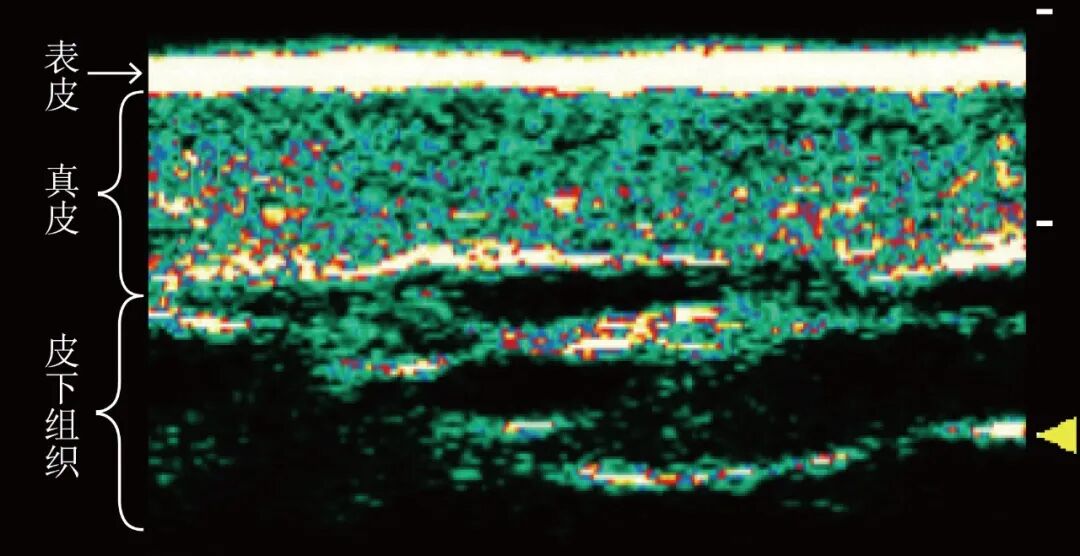

铨影高频超声所配备的8-62MHz超宽频变频探头为例,当对皮肤组织进行扫描时,它能清晰呈现从表皮、真皮至皮下脂肪的各层次图像,操作者能够通过变频来实现对各皮层的精准检测。

图1:皮肤层次图